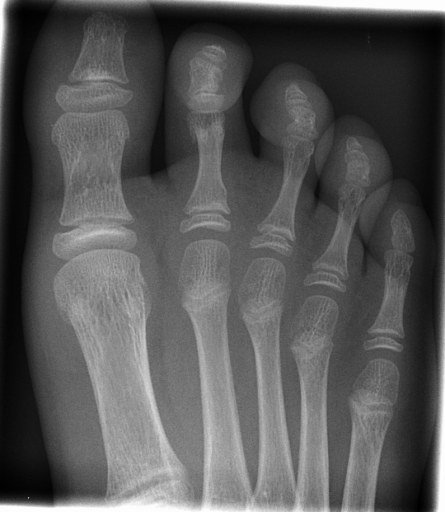

Image Dataset – The Image Retrieval in Medical Applications (IRMA) 2009 database is a collection of 14,410 x-ray images that have been randomly collected from daily routine work at the Department of Diagnostic Radiology of the RWTH Aachen University (Fig. 2). The downscaled images were collected from different ages, genders, view positions, and pathologies [33]. Each image in the dataset has an IRMA code. According to these codes, 193 classes are defined according to 2008 IRMA codes. The IRMA code comprises four axes with three to four positions each: 1) the technical code (T) (modality), 2) the directional code (D) (body orientations), 3) the anatomical code (A) (body region), and 4) the biological code (B) (the biological system examined). The complete IRMA code consists of 13 characters TTTT-DDD-AAA-BBB, with each character in . As many as 12,677 images are separated for training. The remaining 1,733 images are used as test data. In this project, the IRMA 2009 dataset has been used with specified 2008 IRMA labels (consisting of 193 classes) for retrieval purposes. Otherwise, same dataset is utilized with general 2005 IRMA labels (consisting of 57 classes) for classification purpose. 2005 IRMA labels are more general than 2008 IRMA labels because it has been made of 6 characters from top of hierarchical classes, TT-D-AA-B. In 2009 dataset, each image can not have been coded according to 2005 IRMA coding regularity. A total number of 12,631 images from training set and 1,639 images from testing set have 2005 IRMA codes. For this reason, SVM classification is implemented on corresponding images.